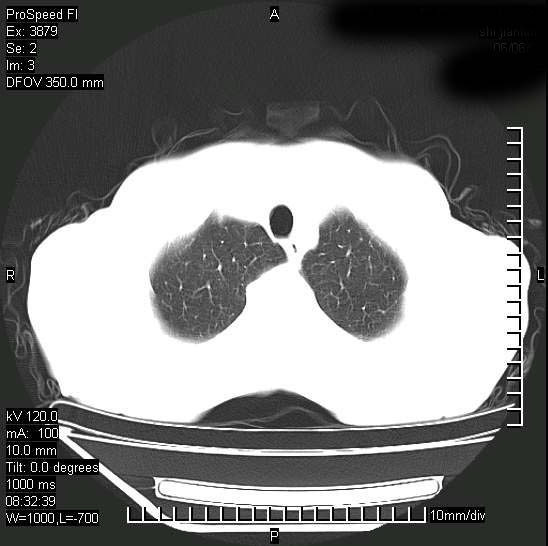

以下是引用37度在2008-6-6 11:20:00的发言:[br]1.包裹性积液,多考虑结核性;[br]2.穿刺术后改变。

以下是引用312nanyang在2008-6-6 15:12:00的发言:[br]基本支持楼主意见[br]疑问?左下肺支气管旁的软组织(16层)密度怎么解释?淋巴结还是斜裂胸膜增厚所致?能否增强进一步检查